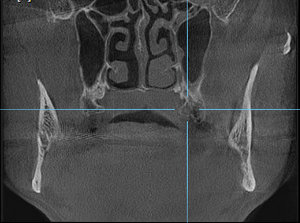

Под новый год заболела челюсть у виска справа (подозреваю, что на фоне проходящего гриппа). Сделал КТ челюсти. Специалистов у нас нет, предложили ехать за консультацией в краевой центр. Можно по снимку определить, что это у меня случилось?

Комментарий №175658 Комментарий №175658 Комментарий №175658 Комментарий №175658

• Описанная проблема может быть связана с височно-нижнечелюстным суставом. Возникнуть симптом может при дегенеративном поражении височно-нижнечелюстного сустава или вследствие других проблем в челюстно-лицевой области (патология прикуса, бруксизм, мышечный гипертонус). Рекомендуем Вам обратиться на консультацию к гнатологу или специалисту в области нейромышечной стоматологии